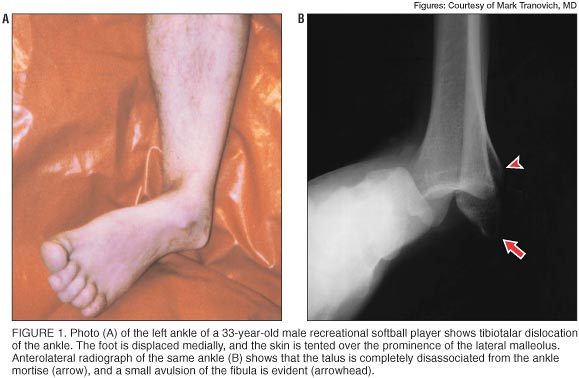

Physical exam. When the patient was brought to the emergency department, his ankle was deformed, with the entire foot displaced to the medial side (figure 1A). The fibula was prominent laterally, causing tenting of the skin. The dorsalis pedis pulse was still palpable. The patient reported paresthesias, predominantly along the tibial side of the foot to the midfoot and plantar region. Paresthesias on the lateral side of the foot were less pronounced. Sensation was normal above the injury. Capillary refill in his toes was good, and no significant swelling was noted. No lacerations or open wounds were present, and he appeared otherwise healthy.

Radiology and diagnosis. Dislocation of the ankle joint and a small avulsion from the distal fibula were seen on standard views of plain radiographs (figure 1B).